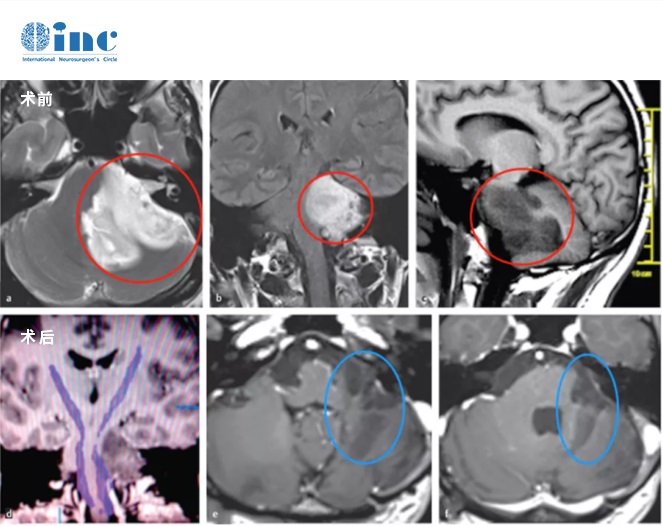

案例3:腦干膠質(zhì)母細(xì)胞瘤

34歲H先生因右半邊臉面癱,左臉麻木、輕度面癱、左邊耳朵也聽不清而去就診,去醫(yī)院查出腦干占位,醫(yī)生建議還是盡早手術(shù),以明確病理進(jìn)行后續(xù)治療。但由于腦干手術(shù)的較其復(fù)雜性,癱瘓風(fēng)險(xiǎn)很高,很多醫(yī)生沒有把握。為追求高質(zhì)量的手術(shù)效果,H先生求診于INC德國巴特朗菲教授進(jìn)行治療。在德國INI國際神經(jīng)學(xué)研究所,教授為H先生切除了較大水平地切除了腫瘤,為避免術(shù)后引起嚴(yán)重的神經(jīng)功能障礙,沒有采取全切。這些神經(jīng)完好無損,沒有并發(fā)癥。術(shù)后輔助其他放療手段,H先生4年內(nèi)復(fù)查病灶穩(wěn)定,且保持了良好生活質(zhì)量狀態(tài)。

腦干膠質(zhì)母細(xì)胞瘤

需要引起高度注意的是,這個(gè)腦干膠母多數(shù)是難以手術(shù)的,因?yàn)槟[瘤往往浸潤性生長,邊界不清,但是不幸中的幸運(yùn),這個(gè)患者腫瘤呈外生性生長,也有邊界,再結(jié)合ini的前沿手術(shù)理念、手術(shù)設(shè)備如術(shù)中磁共振+神經(jīng)電生理監(jiān)測等,所以可以大部分切除腫瘤,結(jié)合患者年輕,又及時(shí)正確規(guī)范的治療,預(yù)后可以達(dá)到4年之久,相比常規(guī)的預(yù)14月左右的生存期預(yù)后,明顯提高不少。